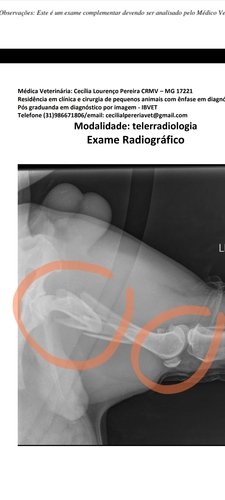

Fui atropelado no dia 17/07. Passei por duas cirurgias. Tive várias fraturas no fêmur e na região pélvica, estou anêmico e com alteração no fígado.